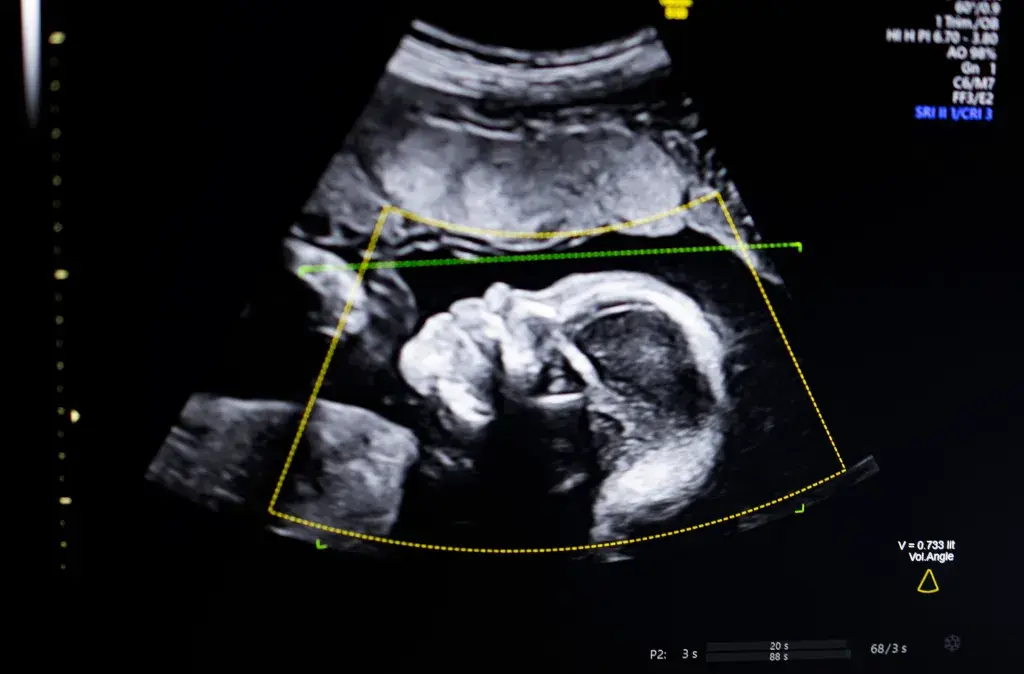

Bustami在接受TechCrunch采访时表示,该软件利用计算机视觉类人工智能技术,用于支持胎儿超声检查中的质量评估、解剖结构完整性评估、自动生成报告,并可与现有临床工作流程进行集成。

他指出,产前超声已成为妊娠监测的“基石”,但图像质量不佳可能导致误诊。公司希望通过该技术提升超声检查质量和一致性。